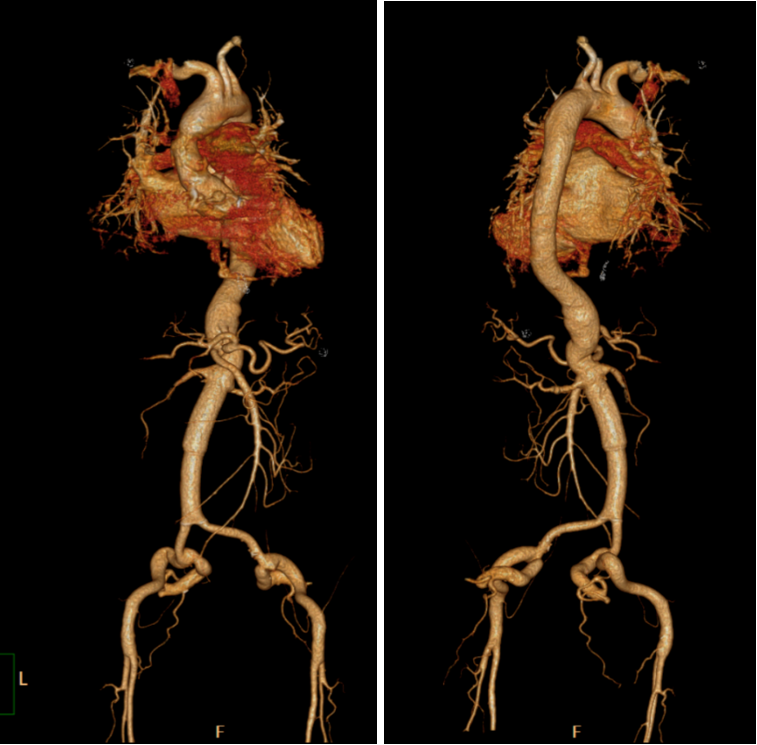

病例1: 降主动脉瘤;一期行开腹内脏动脉去分支(腹腔干、肠系膜上动脉、双肾动脉重建于右髂总动脉),术后6天CTA显示重建血管通畅;

二期(术后第7天)经股动脉置入胸主动脉覆膜支架,锚定于人工血管远端。

术后3年CTA显示支架位置良好,假腔血栓化,现在随访已经13年患者再干预2次(因其他部位病变),目前情况良好。

29岁男性,Bentall术后36天出现夹层累及全胸腹主动脉及左髂总动脉。因脊柱侧弯、胸廓畸形,无法耐受再次开胸。

病例2:Bentall术后36天 夹层TAAA累及左髂总行杂交手术;流入道血管:右髂总动脉;术后8年CTA复查结果良好